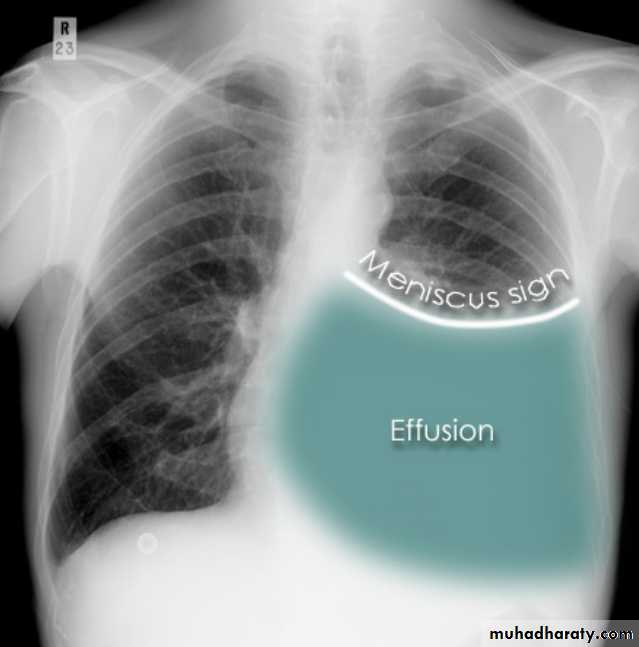

CXR (erect)

Both PA and AP erect films are insensitive to small amounts of fluid. Features include:

blunting of the costophrenic angle

blunting of the cardiophrenic angle

fluid within the horizontal or oblique fissures

eventually a meniscus will be seen, on frontal films seen laterally and gently sloping medially (note:

Pleural effusion